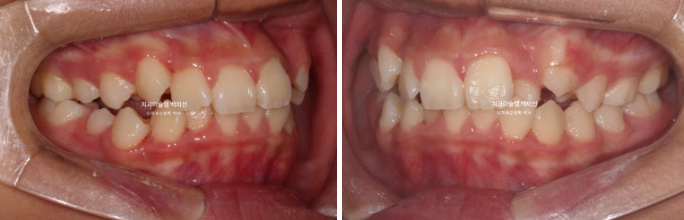

공간부족으로 인한 덧니가 심해 반대교합이 있습니다.

24.02

악궁확장을 통한 덧니 배열을 목표로 인비절라인 퍼스트 교정치료를 권유드렸습니다.

24년 2월부터 9월까지 첫세트의 19개 장치를 모두 낀 후 모습입니다.

24.09

중심선은 개선되었으나 약간의 불일치가 남아있으며 반대교합과 덧니는 모두 개선되었습니다.